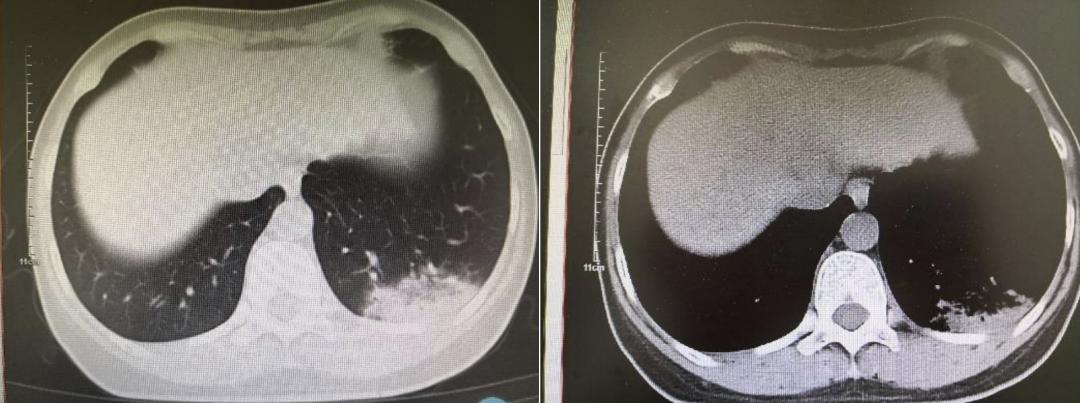

图1.2022年5月18日患者肺部CT影像

3、肺部HRCT(图1)

(2022-5-18,图1)左下肺实变影,考虑炎症,建议治疗后复查。